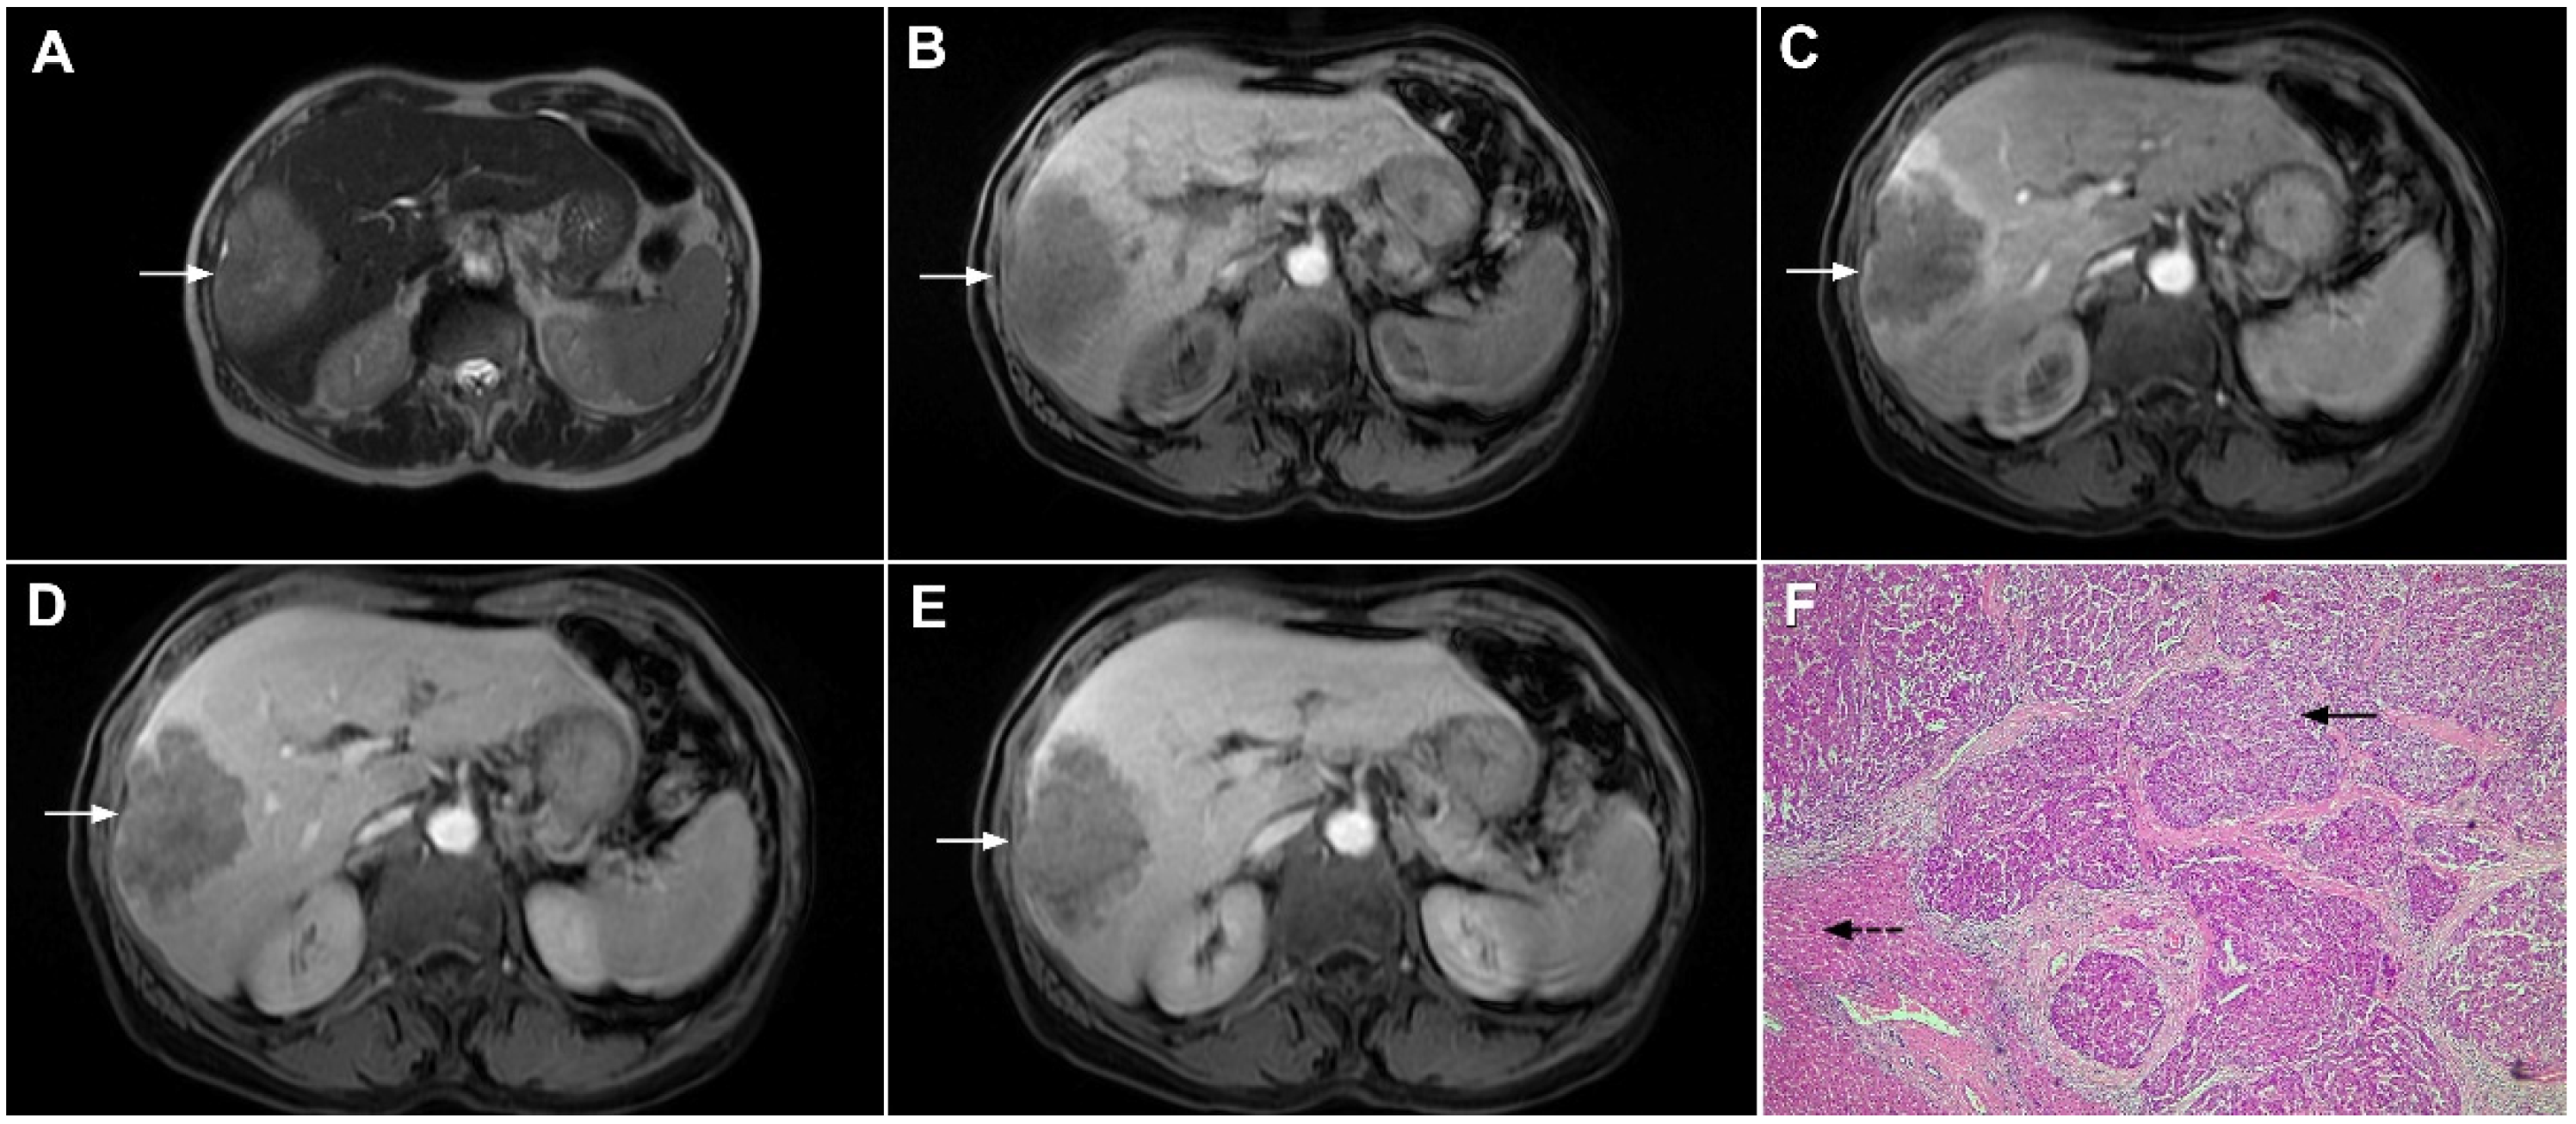

Figure 1.

Typical intrahepatic mass-forming cholangiocarcinoma in 68-year-old woman. On axial T2-weighted image a lobular heterogeneously hyperintense tumor (arrow) is seen, located centrally in the liver segment IVB (A). The lesion (arrow) is hypointense in a plain T1-weighted image (B) with irregular ring enhancements in the arterial phase (C) and progressive enhancement in the portalvenous (D) and delayed phase (E). Note the perilesional biliary dilatation. Hematoxylin and eosin (H&E) staining (F) showed cholangiocarcinoma (arrow) and normal liver parenchyma next to the tumor (dashed arrow); original magnification ×40.